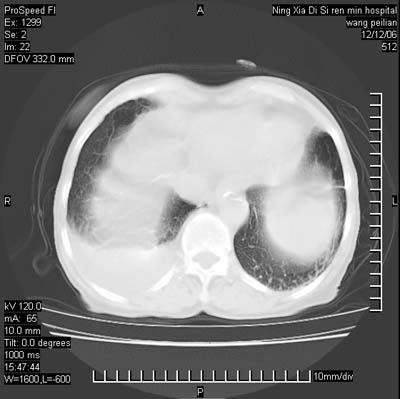

两肺可见多个大小不等的结节,左侧有胸水,纵隔淋巴结增大,考虑是细支气管肺泡癌

两肺尖纤维索状影,两下肺结节块状影,且有钙化灶,右胸腔积液。考虑肺结核并胸膜炎。

双侧肺结核伴右侧胸腔积液.

两肺尖纤维索状影,两下肺结节块状影,且有钙化灶,右胸腔积液。考虑肺结核并胸膜炎肺间质纤维化

两肺以间质性病变为主,并有胸腔积液,考虑结核

考虑:1、慢性支气管炎合并全小叶型肺气肿、间质纤维化;

2、双肺结核;

3、右侧胸膜炎(积液)。

1、双肺继发型肺结核(以纤维、增殖灶为主);

2、右侧胸腔积液;

3、其余符合老年肺改变。

双肺见多个结节状及条索状影,双侧胸腔积液,右侧叶间积液,考虑结核性胸膜炎